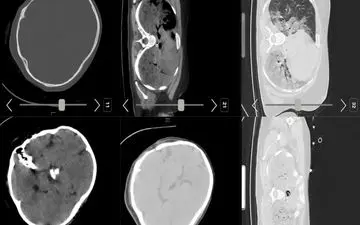

پزشکان متخصص معتقدند تصاویر «سی تی اسکن» منتشر شده از مرحوم امینی گویای این موضوع است که هیچ شواهدی از ضربه به سر و…